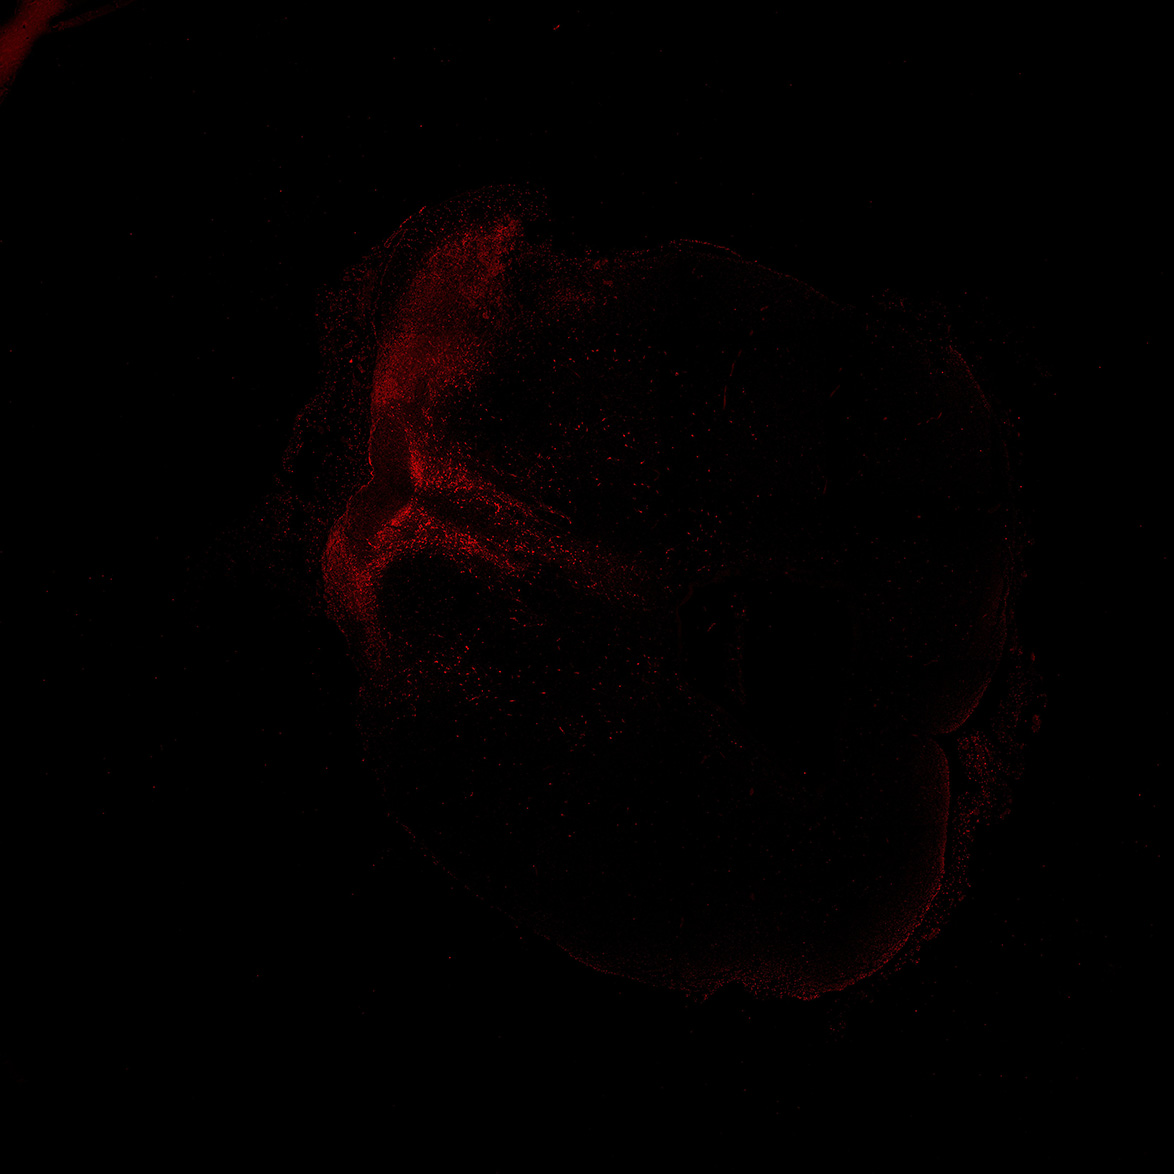

TH

11PCW human midbrain